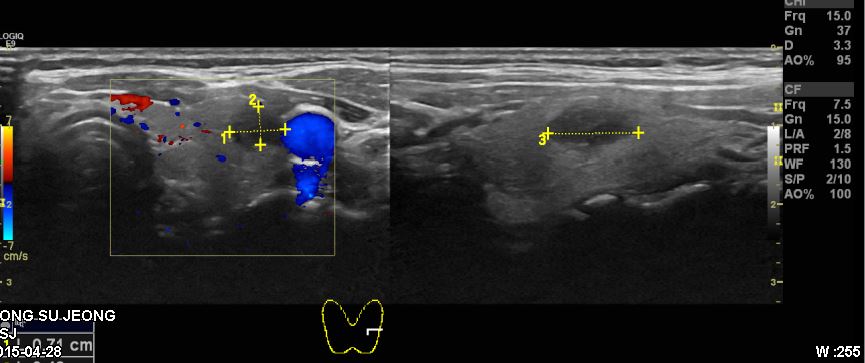

검진상 이상 소견으로 정밀 검사 위해 내원하신 50대 여성 분으로 본원 세포검사 후

좌측 갑상선 유두암 진단 되셨습니다.